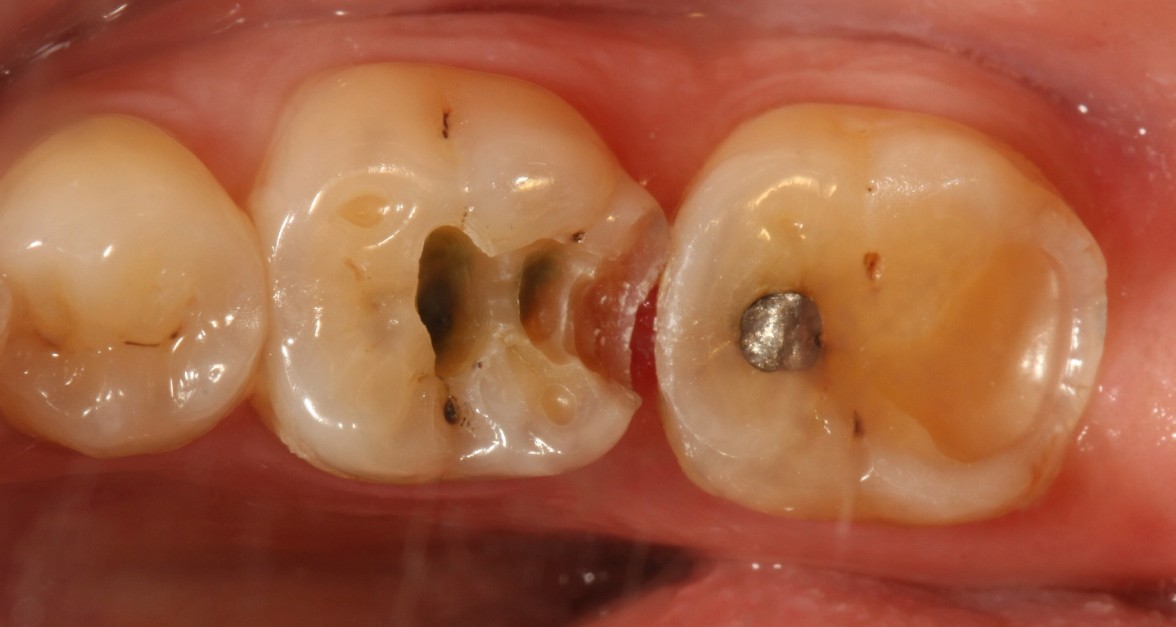

口腔检查时,会经常遇到以前补的银汞合金边缘变色,探有卡顿,形成了继发龋坏,建议重新充填或者瓷嵌体修复;瓷嵌体修复技术,可以非常好的恢复牙体形态和非常密合的边缘,色泽也非常逼真;我们采用CEREC(德国瓷睿刻)椅旁加工技术,达到最佳修复效果!